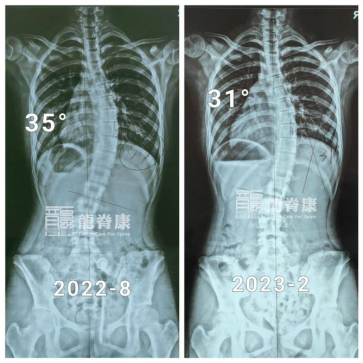

在最初的一年里,小墨坚持每3个月回来复查体态以及调整支具。3个月复查时,脱支具4小时后的X光片显示,她的胸弯度数已经从50°减至39°,且剃刀背都有明显改善,右背部剃刀背由14°减至7°,左腰部剃刀背由12°减至8°。

在接下来的6个月、9个月及12个月的复查里,小墨的侧弯体态也在逐渐改善,侧弯度数也慢慢减少了。

矫正的第二年,无论是她的侧弯度数还是体态,还是有在慢慢好转,只是改善速度明显不及第一年了。

尽管如此,胸弯角度由50°减少至31°的小墨已经能避免了手术治疗;接下来的时间里,在她骨骼发育基本成熟稳定前,小墨还是需要继续配合治疗以及及时复查,除稳定侧弯减少进展的风险外,她还能为进一步改善体表再努力一把。